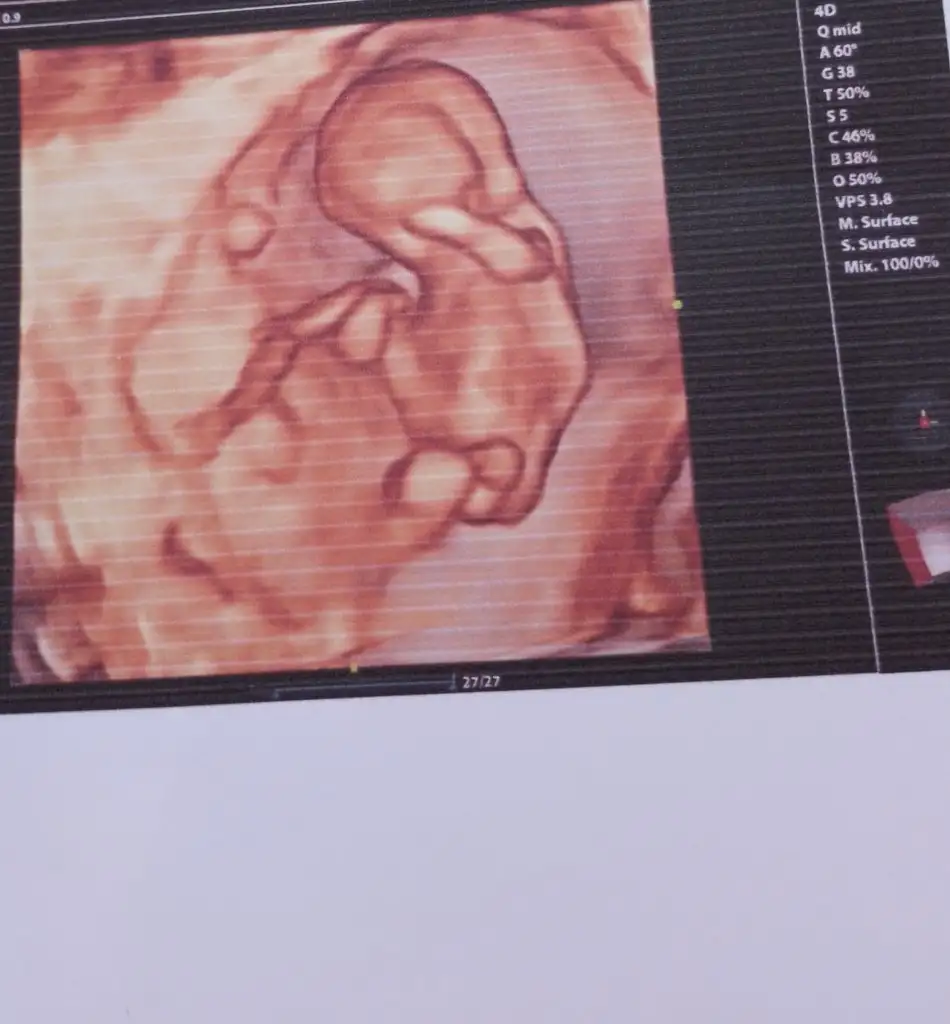

merhaba kızlar benimde burda 12+5 görüntüler ama doktor çok erken dedi yorum yapmadı acaba tahmininiz varmı ???

WhatsApp Image 2024-03-12 at 15.33.06.webp

merhabalar 12+ 2 günlük cinsiyet tahmininde bulunabilirmisiniz cok merak ediyorum

Eklentiler

• 20240402_102841.webp

20240402_102841.webp

19,2 KB · Görüntüleme: 63

12+3 bakar mısıznz doktor net bir şey demedi

• IMG_2270.webp

IMG_2270.webp

49,9 KB · Görüntüleme: 53